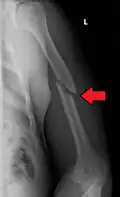

A spiral fracture of the distal one-third of the humerus shaft -